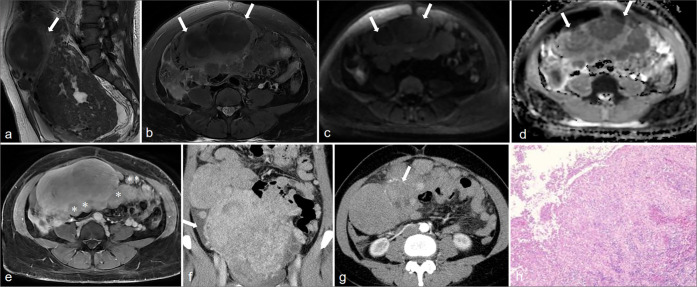

Results: All the 10 LPD patients presented with multifocal lesions in the abdomen and pelvis, and 7 of them had a history of hysteromyoma surgery. The number of lesions was all ≥2, most of them were round or quasi-circular, with clear boundaries and smooth edges, did not invade the neighboring parenchymal organs, with a length of about 1.5~16.8 cm. The lesions were located in the pelvic cavity in 6 cases, the abdominal wall in 6 cases, the intestinal wall in 3 cases, the rectouterine pouch in 1 case, the omentum in 5 cases, the abdominal cavity in 1 case, and the mesentery in 1 case. There were 7 cases with minimal pelvic fluid and 1 case with liver spread. CT showed circular solid nodules with clear boundaries. The density of small lesions was homogeneous. Cystic changes were observed in some large lesions. On MRI, T1-weighted imaging showed hypo to isointense, T2-weighted imaging (T2WI) mostly showed hypointense, and T2WI in some large lesions showed slightly high signal intensity, diffusion-weighted imaging signal intensity was not higher than that of myometrium, apparent diffusion coefficient showed isointense, and solid components of the lesions were significantly more homogeneous enhanced after enhancement, and the enhancement degree was similar to that of normal myometrium.